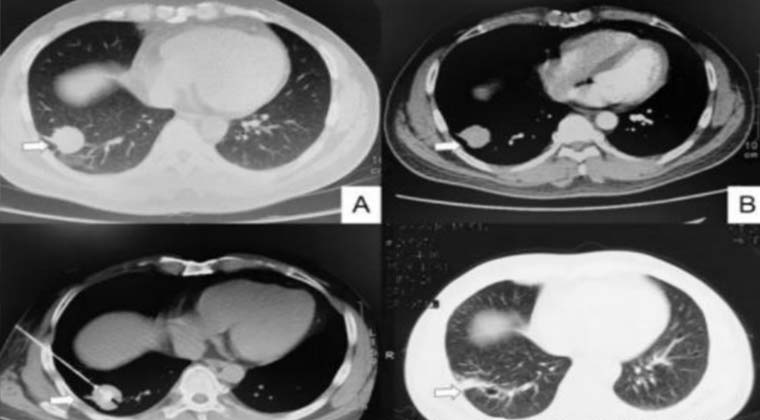

Пациент страдал аденокарциномой правой нижней доли легкого диаметром 3 см (верхние левое и правое изображения).

Микроволновая абляция была выполнена под местной анестезией (нижнее левое изображение).

При повторном обследовании через 3 месяца очаг полностью некротизирован с фиброзными изменениями.

На сегодняшний день пациент живет более 3 лет без рецидива опухоли.

До лечения После лечения